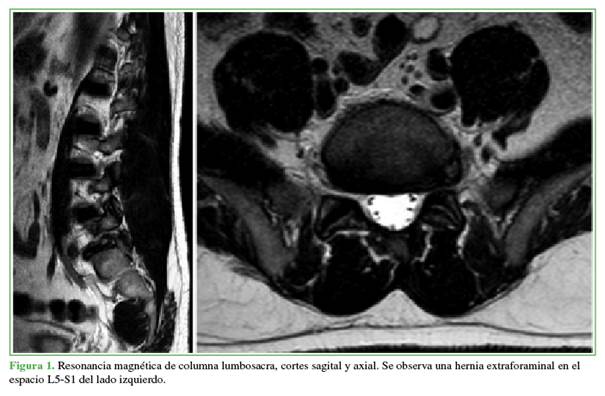

Bajo anestesia general, se ubica al paciente en decúbito ventral, y se procede al embrocado con clorhexidina y a la colocación de campos quirúrgicos para el abordaje posterior lumbar. Mediante radioscopia directa en posición de frente, se marca con una aguja 16 G en la punta de la faceta articular superior de S1 izquierda (Figura 2). Se realiza la incisión cutánea de 8 mm y la apertura de la fascia lumbar. A continuación, se desciende la cánula de trabajo junto con un endoscopio transforaminal Elliquence®, con óptica de 30º. Se procede al fresado lateral de la faceta de S1 con una fresa con adaptador para cirugía endoscópica. A medida que se genera el espacio en dirección ventral, se desciende la cánula de trabajo. Una vez localizada la cortical anterior de la faceta, se la reseca con una pinza Kerrison Rongeur de 3 mm. Luego, se efectúa un control radioscópico para asegurarse de la correcta dirección de trabajo (Figura 3).